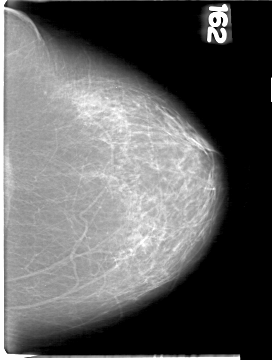

D_4094_1.LEFT_MLO

LEFT_MLO LINES 5311 PIXELS_PER_LINE 3961 BITS_PER_PIXEL 12 RESOLUTION 43.5 NON_OVERLAY